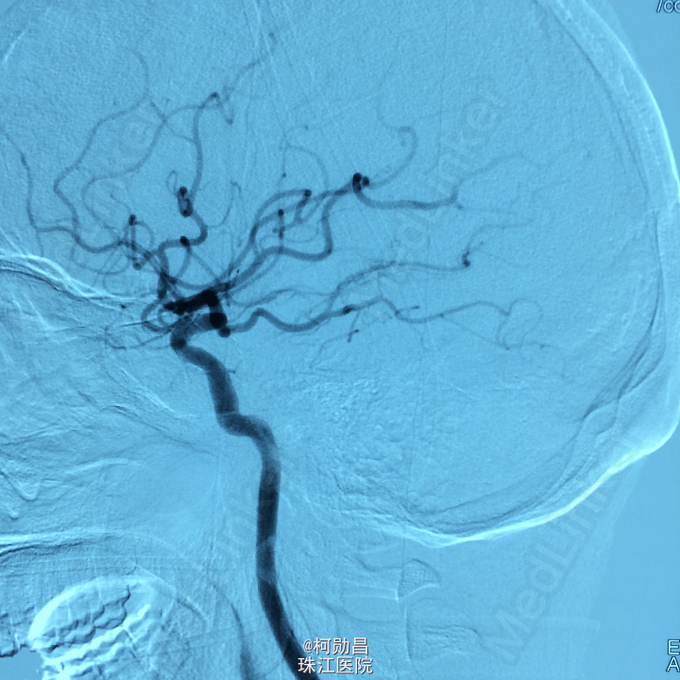

查体:痉挛性截瘫,肌力 4/5 级,马鞍区感觉减退,肛门括约肌张力下降, 腱反射活跃。 辅助检查:腰椎穿刺脑脊液检查示脑脊液蛋白 53mg/dL,葡萄糖 59mg/dL,细胞学检查可见成熟的淋巴细胞,寡克隆区带阴性,免疫球蛋白 IgG 指数为 0.58。布氏杆菌、梅毒、脑脊液 / 血清血管紧张素转换酶水平、结核杆菌聚合酶链反应、单纯疱疹病毒、EB 病毒、水痘 - 带状疱疹病毒,包柔螺旋体(莱姆病)血清学检测均为阴性。结合患者的脊髓 MRI 表现,初步诊断为脊髓血管畸形

诊断:硬脊膜动静脉瘘 处理:予全麻下行栓塞治疗,选择予 withn-butyle-2-cyanoacrylate(医用胶)完全闭塞 。